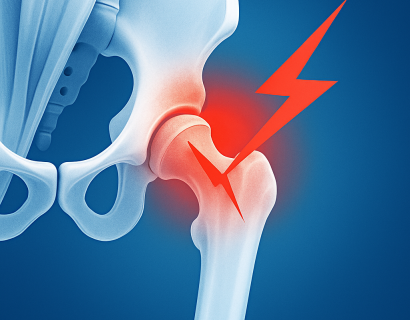

Хруст в тазобедренном суставе может возникать в разном возрасте и при самых разных обстоятельствах: во время движения, после физической нагрузки, при сгибании ноги или даже в покое.